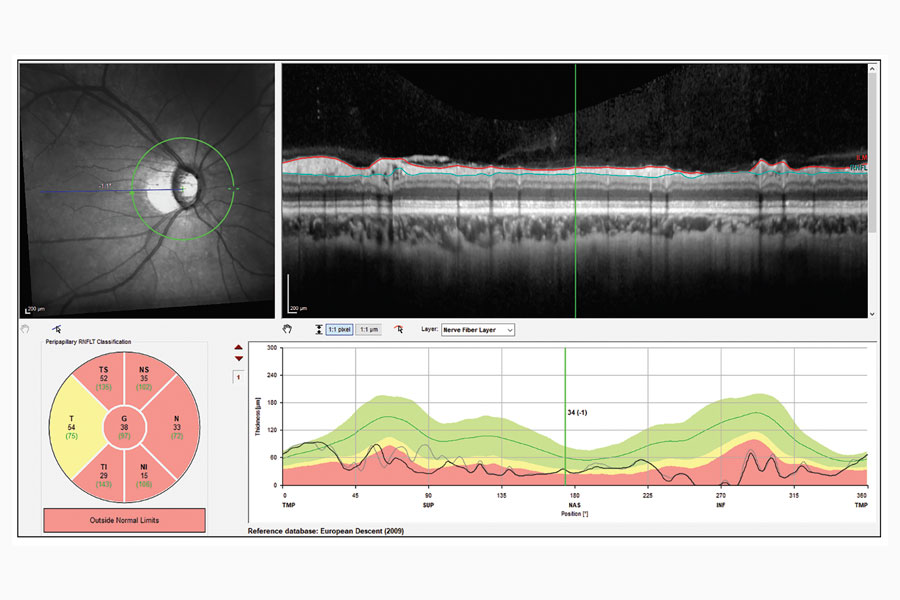

Diagnóstico del glaucoma en pacientes con miopía alta

Read moreDetailsPor Andrew Beers, editor asociado Los dispositivos de OCT son herramientas poderosas para los oftalmólogos, pero ...